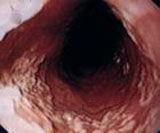

對104例NCCP患者進行24小時食管內pH監測時發現,有48%的患者有異常的酸暴露。NCCP的患者在進行胃鏡檢查時發現食管黏膜糜爛者占10%~70%。有研究顯示,套用以質子泵抑制劑(PPI)為主的抗反流治療,對80%的反流性食管炎或24小時食管內pH監測異常(pH<4)的患者治療有效,提示酸反流是發生NCCP症狀重要的病理生理學基礎。

1.胃鏡檢查:胃鏡檢查對NCCP患者的診斷價值是有限的,其價值主要在於通過胃鏡檢查可以在GERD相關NCCP中除外Barrett食管,確定反流性食管炎的診斷。